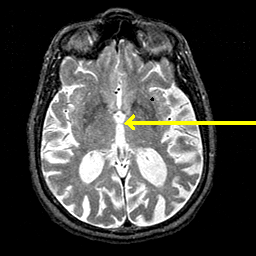

Alzheimer's disease MR T2-weighted -- Slice #24

Tour 1: Next/Previous/Start: The third ventricle is enlarged and contains a barely visible massa intermedia.